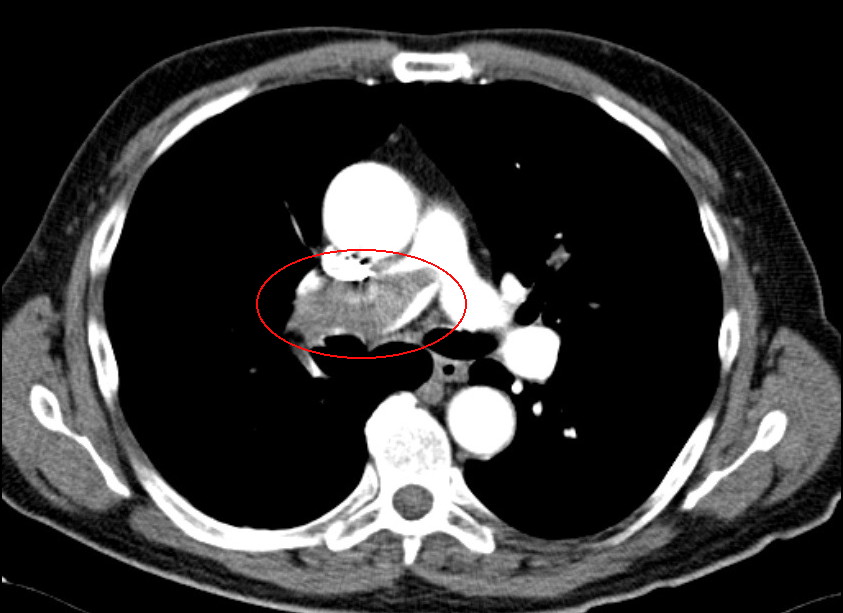

Lungenembolie mit Nachweis eines großen Thrombus innerhalb der rechten Pulmonalarterie